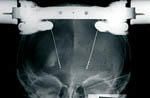

Die Operation erfolgt in zwei Schritten: Zunächst werden beide Elektroden in örtlicher Betäubung implantiert. Dazu wird ein Metallring auf dem Kopf fest angebracht. Mit diesem Stereotaxiering werden spezielle Computertomogramme und Röntgenaufnahmen angefertigt, mit deren Hilfe die Koordinaten der Zielpunkte in den Basalganglien berechnet werden. Die Elektrode wird schmerzfrei und zielgesteuert (stereotaktisch) in die zuvor definierten Hirnzentren eingeführt. Auch während der Operation wird die Lage der Elektroden mit Röntgenaufnahmen regelmäßig kontrolliert.